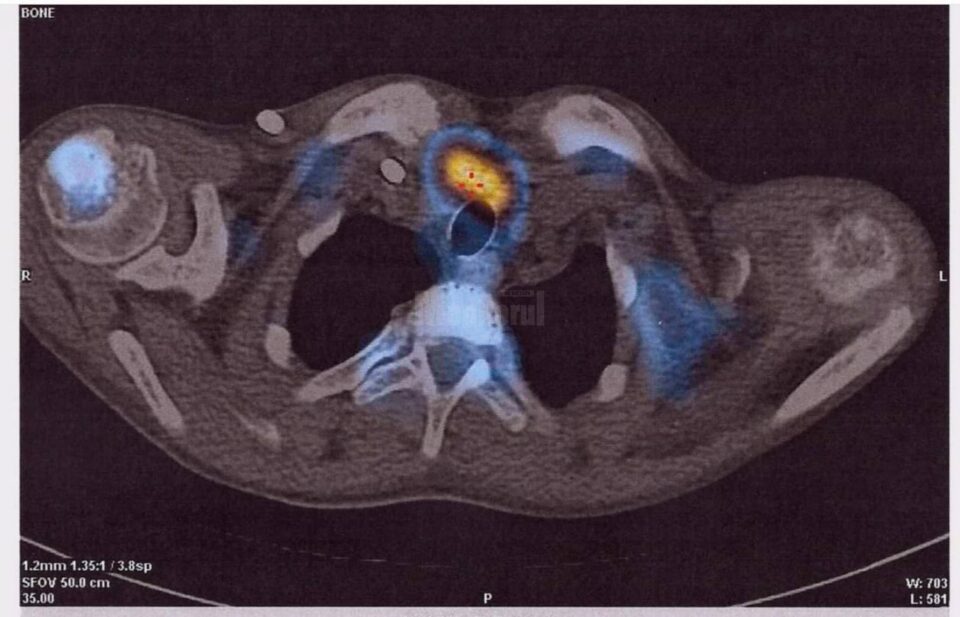

O echipă medicală multidisciplinară formată din dr. Rareș Voinea, dr.Mihaela Guțu, dr. Mihai Guțu, dr. Ionuț Cordoș, dr. Adrian Nistor și dr. Ruslan Gorceag a realizat o nouă premieră la Spitalul Județean de Urgență „Sfântul Ioan cel Nou” Suceava – prima paratiroidectomie subtotală (îndepărtarea unor porțiuni din glandele paratiroide), la un pacient în vârstă de 19 ani. Managerul spitalului, dr. Alexandru Calancea, a transmis, printr-un comunicat de presă, că pacientul a fost diagnosticat la sfârșitul anului 2020 cu boală cronică de rinichi, în stadiul terminal, și era inclus în programul de hemodializă. O complicație frecventă a acestei boli este creșterea glandelor paratiroide, ce determină modificări osoase. „Pe fondul acestora pacientul a prezentat o fractură spontană de col femural, rezolvată prin protezare de către medicul ortoped dr. Rareș Voinea”, a arătat dr. Calancea. Acesta a explicat că evaluarea glandelor paratiroide s-a realizat cu ajutorul medicinei nucleare, de către dr. Mihaela Guțu și dr. Mihai Guțu, prin SPECT-CT, identificându-se astfel cu exactitate locația și mărimea acestora. Ulterior, echipa chirurgicală, formată din dr. Ionuț Cordoș și dr. Adrian Nistor, a efectuat prima paratiroidectomie subtotală la Suceava. Pacientul a fost urmărit în continuare în secția de Anestezie Terapie Intensivă, sub coordonarea dr. Ruslan Gorceag, a mai spus dr. Alexandru Calancea.